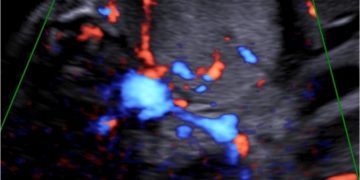

Casi del Mese di Marzo 2023

Cari soci, finalmente online le soluzioni dei casi per il mese di Marzo!!! Grazie a Ilaria Fantasia e Gabriele Saccone!! Caso 1 [pdf-embedder url="https://www.sieog.it/wp-content/uploads/2023/03/caso-clinico-Fantasia-risposta-marzo-2023.pdf" title="caso...